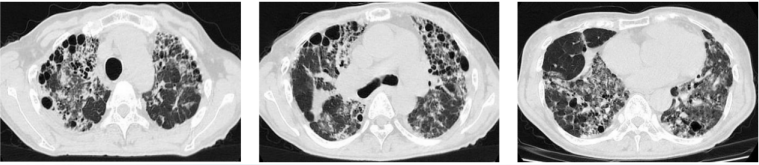

例如文献报道中的Case 3:男性,61岁,2018年3月4日行双肺移植术;移植前3个月曾发生烟曲霉菌感染,应用伏立康唑治疗。移植术后67天出现夜间呼吸困难、伴咳嗽、黄黏痰、双下肢水肿,需应用无创呼吸机辅助呼吸。胸部CT如图19所示。

图片

19  文献报道小囊菌属/帚霉属感染患者的胸部CT

注:A:2018年5月22日胸部CT显示双肺下叶沿气道分布的多发小结节影。B:2018年8月30日胸部CT相对正常。

气管镜下示大量灰黄黏痰附着于双主支气管吻合口附近及右肺上叶、中叶开口,无法完全清除(图20)

20  文献报道小囊菌属/帚霉属感染患者气管镜下表现

注:A:2018年5月22日支气管镜检查发现各叶段均有大量黄脓性黏液痰,在主支气管吻合口和右肺上、中叶开口处均观察到大量黄棕色假膜,无法完全清除。B:2018年8月30日支气管镜检查结果正常。